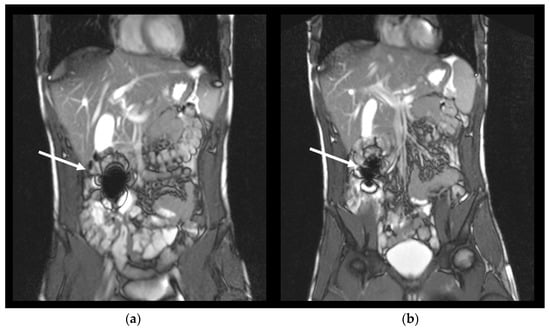

1. Introduction

2.5. Magnetic Resonance Imaging Sequences

2.6. Image Analysis

2.7. Capsule Evaluation Criteria